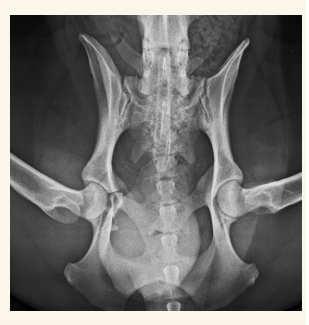

Pelvis

Fracturas y neoplasias lo mas comun. Hacer proyecciones LL, VD y Obliqua

- Ventro-dorsal: Extender extermidades y traccionar, sin rotación axial, paralelas a la mesa, buscamos que la rotula se superponga con el surco troclear. Posicion de rana si es una fractura pelvica

- Latero-Lateral: Esponja de gomaespuma entre rodillas, estirar extermidades posteriores a caudal

- Fracturas pélvicas (generalmente múltiples y afectan a tejido blanco coetáneo)

Displasia de cadera:

- Más en perro que en gato

- Pasa de Laxitud articular a subluxación a EDA secundaria

- Incluir la pelvis, femur y rotulas en radiografia.

- Signos radiográficos típicos según el grado ( A---E ) Siendo A un animal sano y E una enfermedad muy avanzada